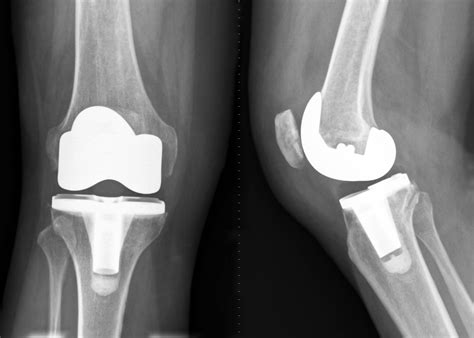

2. Total Knee Replacement (Arthroplasty)

When the knee joint is severely damaged by osteoarthritis, rheumatoid arthritis, or post-traumatic injury, a total knee replacement is often the recommended solution. During this surgery, the damaged cartilage and bone are removed from the surface of the knee joint and replaced with metal and high-grade plastic components.

This surgery aims to alleviate pain, correct deformity, and restore function. Modern implants are designed to mimic the natural movement of a healthy knee, providing long-term relief for many patients.